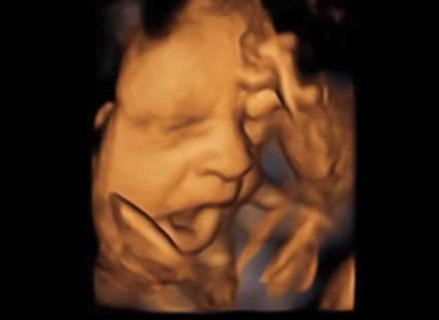

Tras estudios de ultrasonido computarizado en 4D de 15 fetos sanos, realizados por investigadores de la Universidad de Durham y la Universidad de Lancaster, se llegó a la conclusión que el bostezo es un proceso de desarrollo que podría dar a los médicos otro índice sobre la salud de un feto.

Pero la nueva investigación distinguió claramente un “bostezo” de una “apertura de la boca sin bostezo “, basándose en la duración de la apertura de la boca. Los investigadores hicieron esto mediante el uso de las secuencias de vídeo 4D para examinar de cerca todos los acontecimientos que se sucedían cuando el feto movía su boca.

Los resultados de este estudio demuestran que el bostezo se puede observar en fetos sanos y extiende la investigación previa sobre el bostezo fetal.